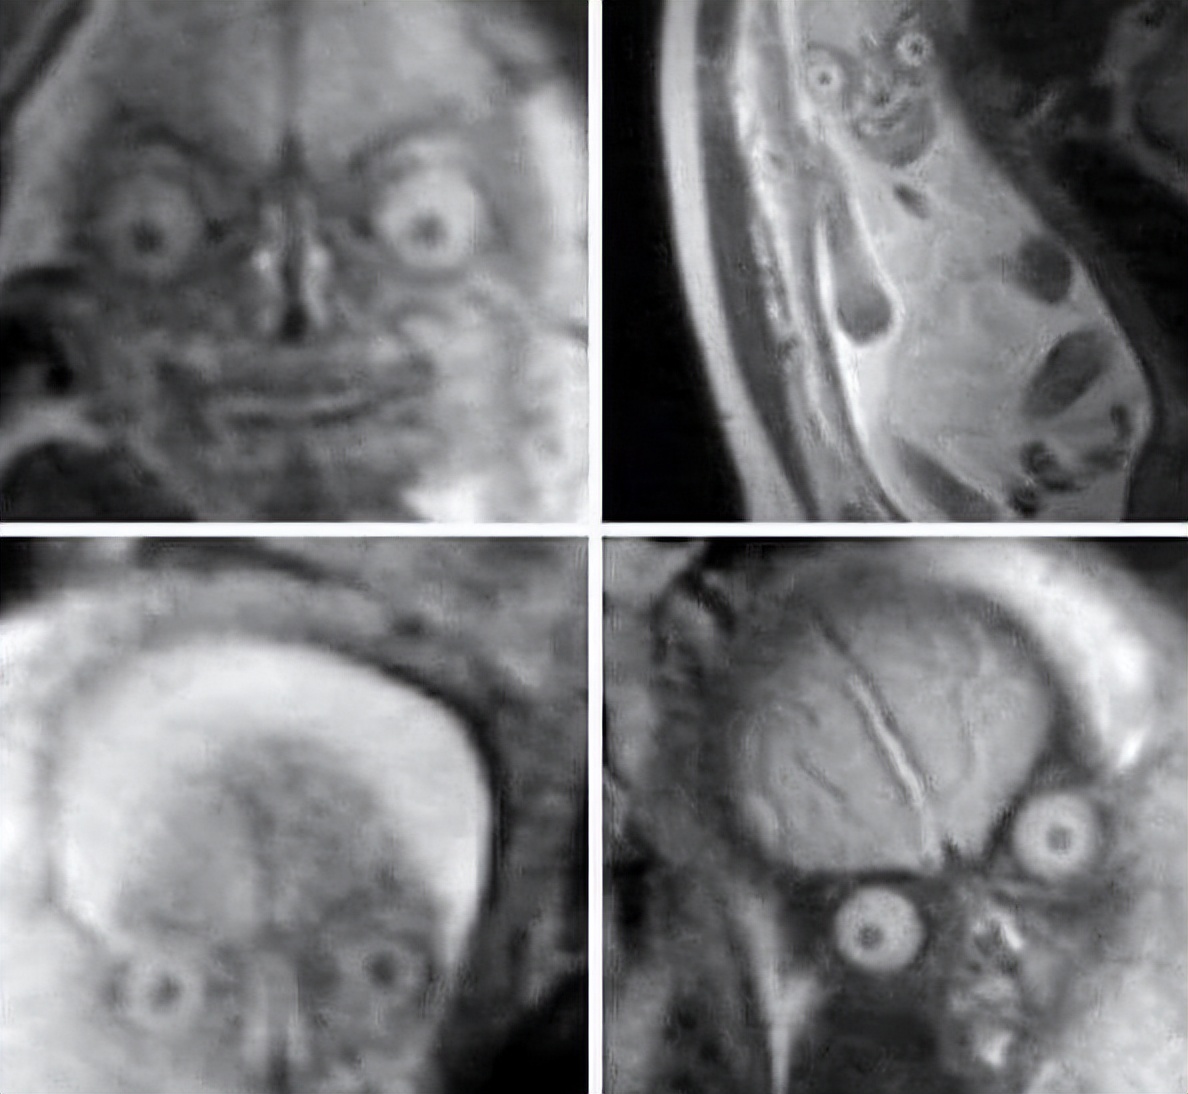

医生不对孕妇进行核磁共振检查的真正原因

如果您怀孕并需要进行核磁共振检查,可能会选择不看婴儿的样子。意识到你正在孵化一个看起来像恶魔的外星人,这将是非常可怕的。这就是为什么医生通常不鼓励在怀孕期间进行 MRI 检查的原因。尽管如果您参与其中,对您或婴儿没有任何已证实的风险,但看到胎儿的样子令人恐惧。这张图片可能很难看清,所以祝你好运。

当然,这个形象是相当可怕的,但希望这是你有生之年从未体验过的。至于一直处理这些核磁共振扫描的医生,真为他们感到抱歉。